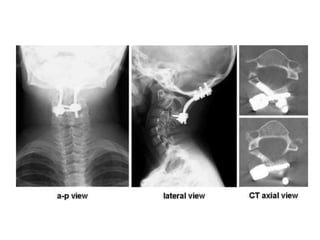

Radiological Assessment • Cervical–X- Ray Lateral A-P especially (( Odontoid # type 2 )) Open mouth • CT thin cuts with reconstruction ( sagittal, Coronal ) • MRI

Surgical stabilization

• C1 – type II odontoid combination # with d >

5mm.

• C1 – hangman combination # C2-3 angulation

> 11 degree